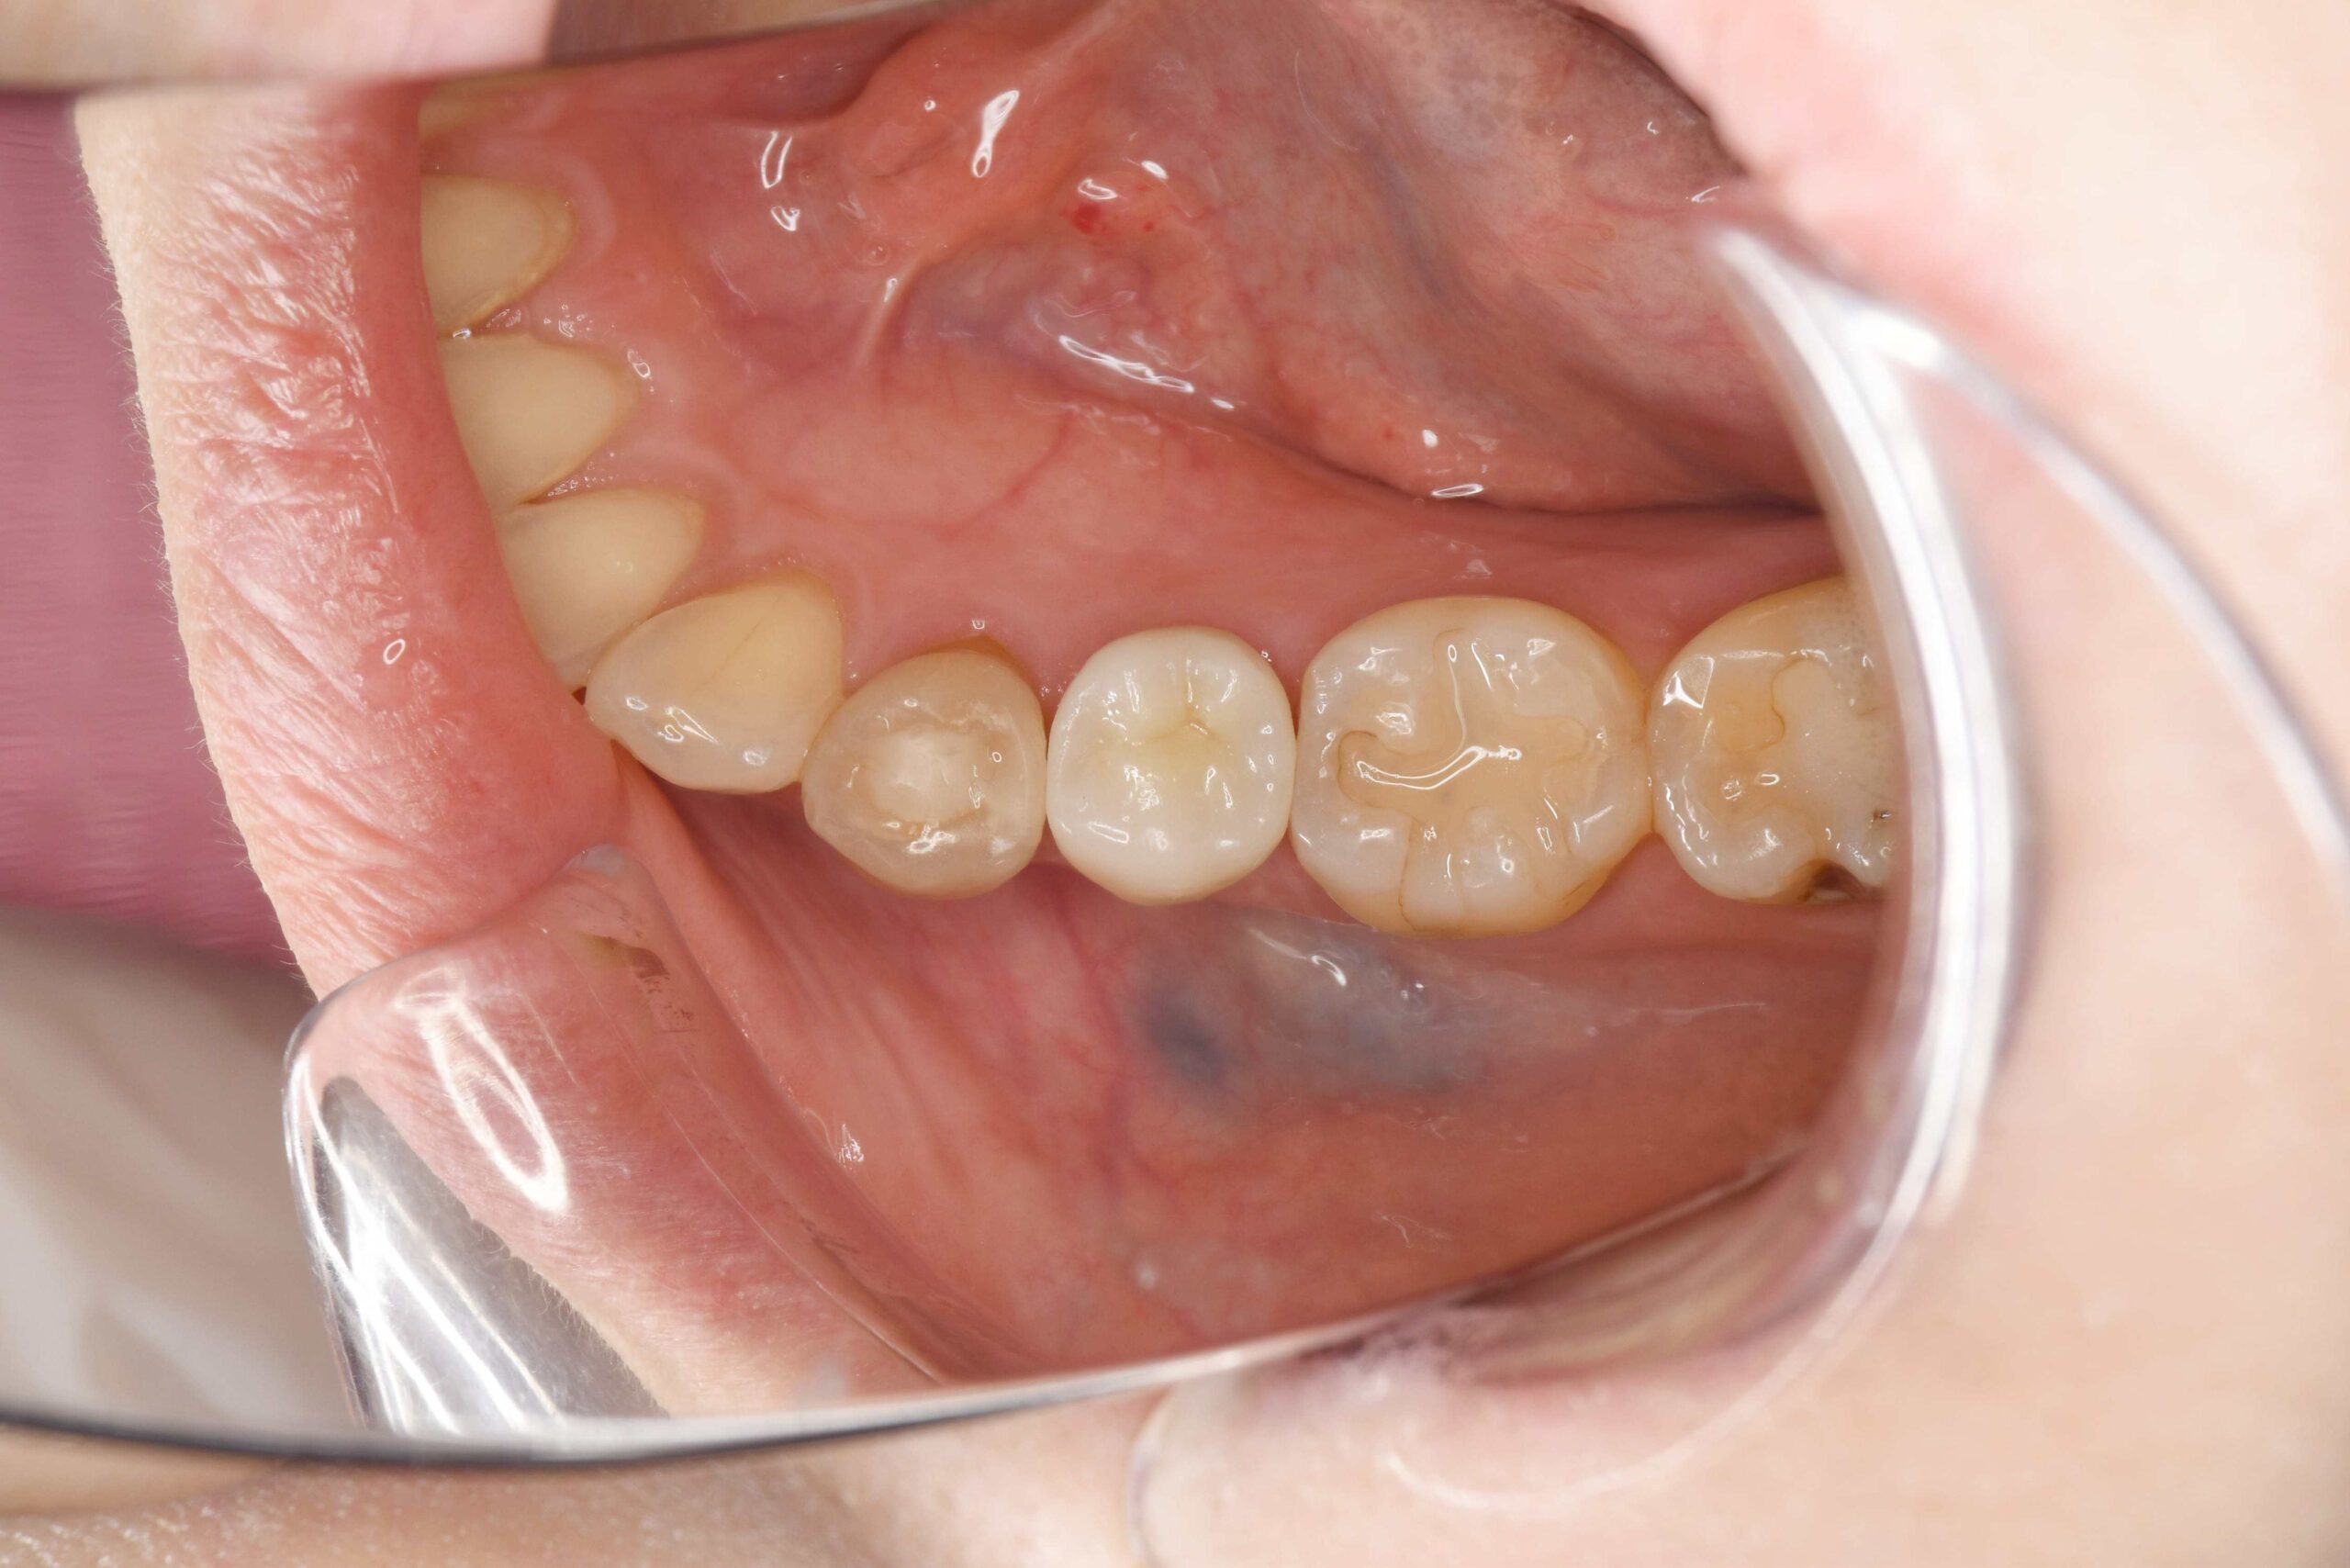

他院に通われていた方ですが、虫歯の再発が多いため今後は再発のリスクとアレルギーの心配が少ない治療法を受けたいとのことで来院されました。

| 銀歯が被っている部分をジルコニアにて被せ物処置を行なった |